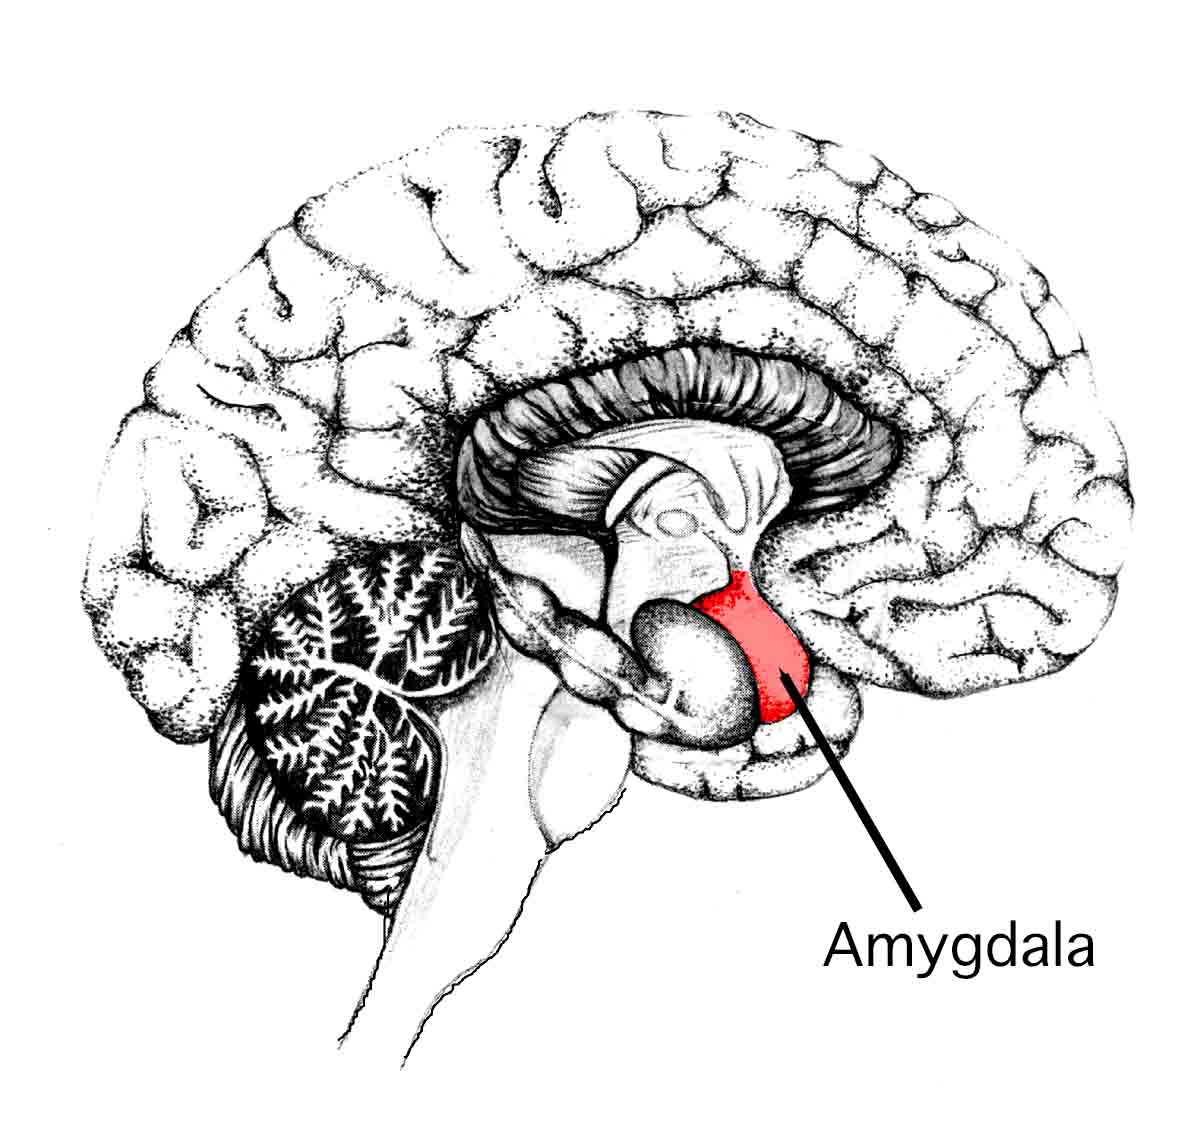

Amygdala is that part of brain which is an almond-shaped mass of nuclei. It is responsible for various hormonal secretions, emotional responses, and memory function. It is involved in fear conditioning (a behavioral paradigm in which organisms learn to predict aversive events) or the associative learning process by which we learn to fear something.

The amygdala is an important structure located in the anterior temporal lobe within the uncus (an anterior extremity of the parahippocampal gyrus). The amygdala makes reciprocal associations with the central nervous system with regions including the thalamus (in the dorsal part of the diencephalon), hypothalamus (in the dorsal part of the diencephalon), septal nuclei (medium-size neurons), orbital frontal cortex (the area of the prefrontal cortex that sits just above the orbits), cingulate gyrus (he curved fold covering the corpus callosum) hippocampus, parahippocampal gyrus (grey matter cortical region of the brain that surrounds the hippocampus and is part of the limbic system), and brain stem.

The amygdala comprises of 2 major regions:

- Centro-corticomedial (central, cortical, and medial nuclei) – This activates the body’s natural instinct of “fight or flight”

- Basolateral (lateral, basal, and accessory basal nuclei) – stimulates fear response

Amygdala

It is located close to the hippocampus deep within temporal lobes